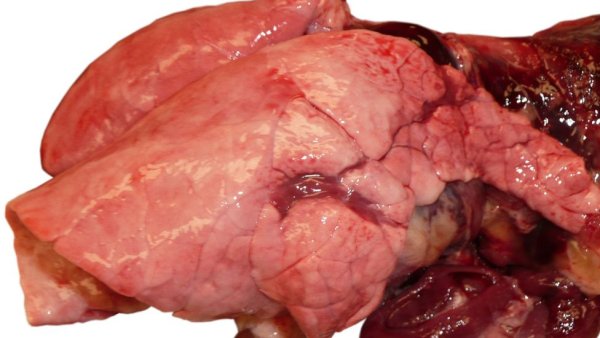

Uno de los retos cuando se trabaja en la eliminación de una enfermedad es asegurarse de que el patógeno ha sido verdaderamente eliminado de la explotación.